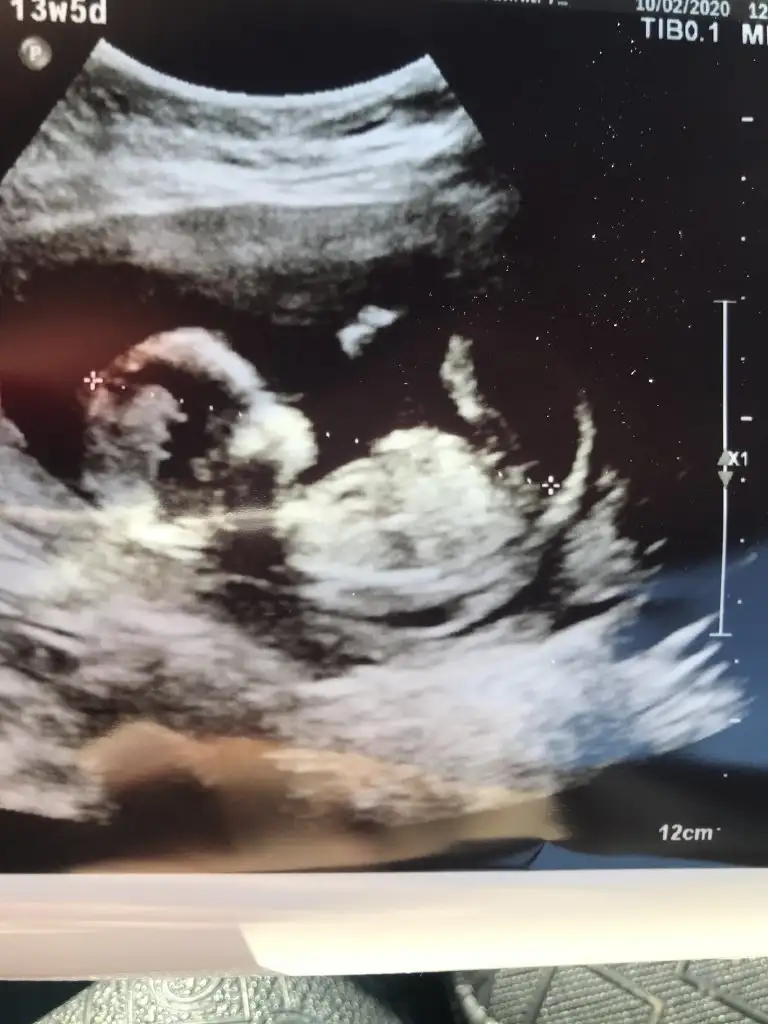

Tamam canım paylasirim 5 hafta sonra :) uzun bi süreMaşallah prensese aynen saglıkKese bazen tutmuyor siz 11 yada 12 olunca tekrar paylaşın

Teşekkur ederim oyunuz içinErkek gibi gibi çok net değil 12+ usgde paylaşın

Sanki kız gibi gibi nubu karanlık kalmış başka usg varsa paylaşın 11 de olabilir12+3 haftalığız bizde tahmin alabilir miyiz?

Teşekkür ederim. Bir de buna yorum yapar mısınız arkadaşın. 12 haftalıkErkek gibi gibi çok net değil 12+ usgde paylaşın

Kız gibi nub çok karışık çıkmış umarım yanılmıyorumdurTeşekkür ederim. Bir de buna yorum yapar mısınız arkadaşın. 12 haftalık